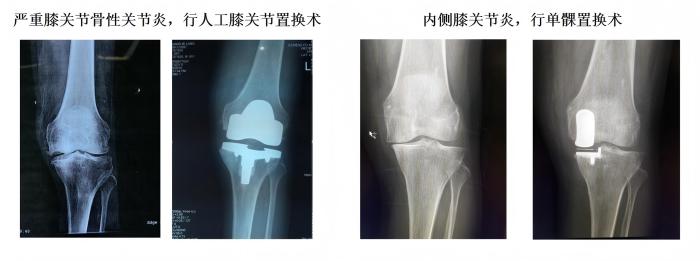

学科简介:跳蛋视频 骨科是集医疗、教学、科研的重点科室,2018年评为中国创伤救治中心建设单位,2019年评为福建省骨科联盟成员单位、厦门市医学优势亚专科。科主任个人获得厦门市政府拔尖人才,厦门市劳模等荣誉。目前设有关节运动医疗组、骨折创伤医疗组、脊柱医疗组、小儿骨科医疗组,常规开展髋关节、膝关节置换,单髁置换,反肩置换,髋膝关节翻修术,胫骨高位截骨矫形,椎间孔镜髓核摘除、脊柱UBE镜下融合,肩关节镜肩袖修复、膝关节镜前后交叉韧带重建,复杂骨盆骨折、胫骨平台骨折复位固定。于国内外期刊发表专业学术论文累及50余篇,SCI 8篇。

1、常规完成复杂全髋、膝关节置换手术(水泥型、生物型)、单髁置换手术、胫骨高位截骨手术、复杂保髋手术、股骨头坏死综合治疗、高龄老人髋部骨折综合治疗。